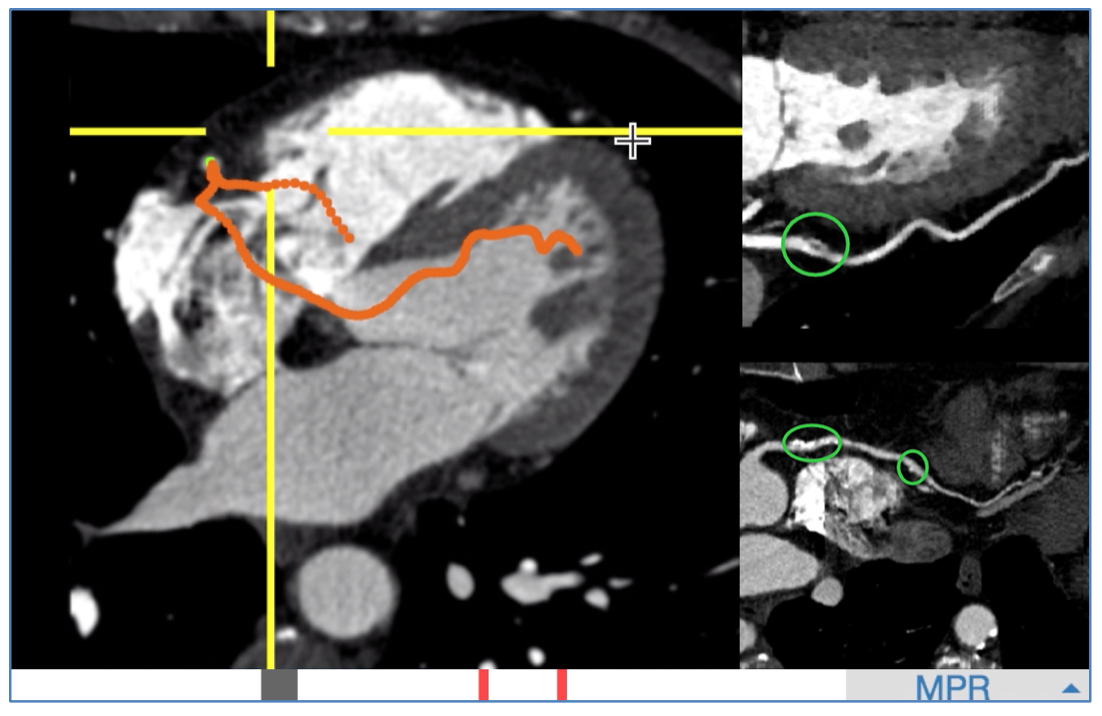

阿里AI在0.5秒内全自动提取的单根心脏冠脉,医生可从重建的影像上快速发现病灶。右上为血管上的软斑块,右下为钙化斑块。